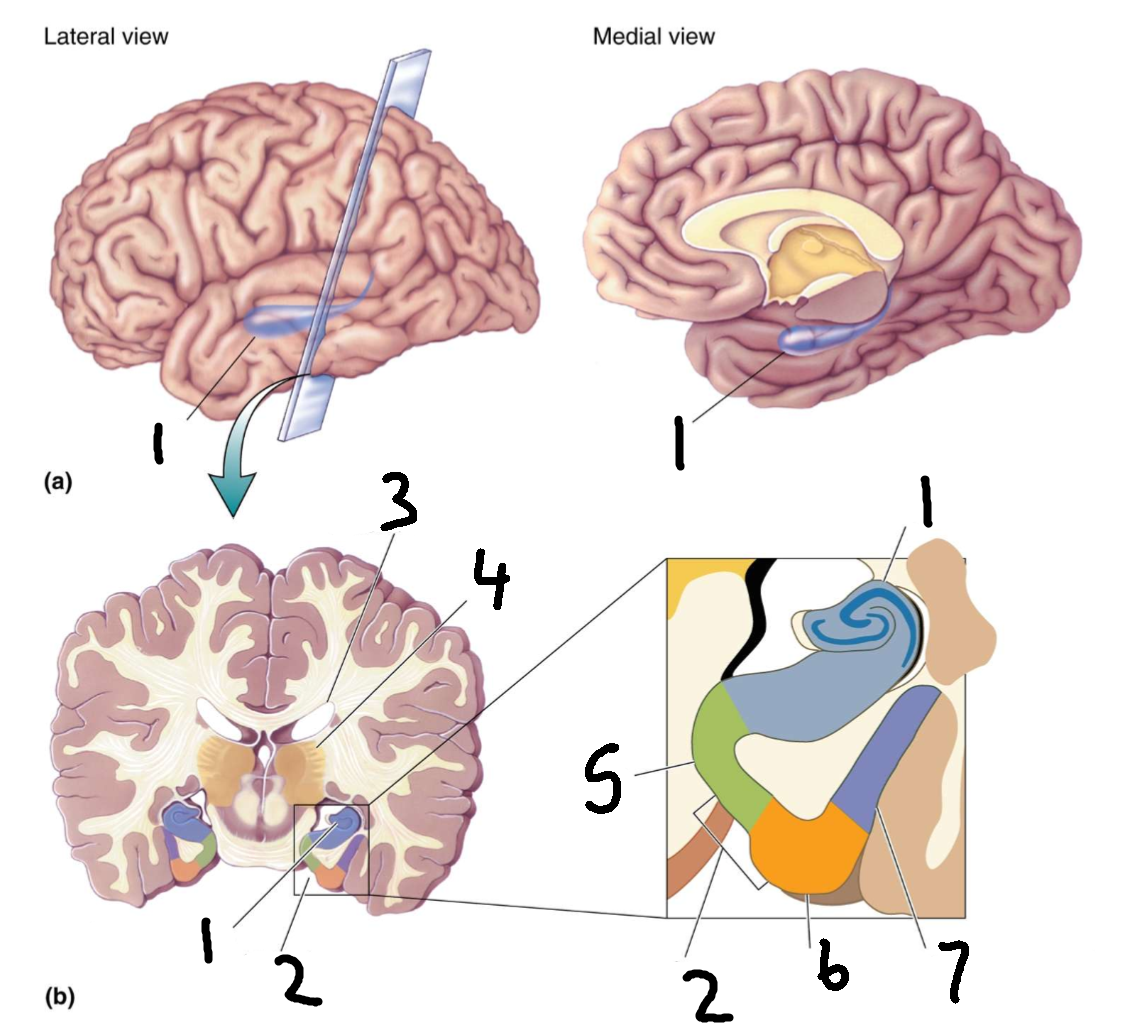

What is 1?

cingulate gyrus

What is 2?

corpus callosum

What is 3?

fornix

What is 4?

cut edge of midbrain

What is 5?

parahippocampal gyrus

What structure is this?

hippocampus

What is 1?

hippocampus

What is 2?

rhinal sulcus

What is 3?

lateral ventricle

What is 4?

thalamus

What is 5?

entorhinal cortex

What is 6?

perirhinal cortex

What is 7?

parahippocampal cortex